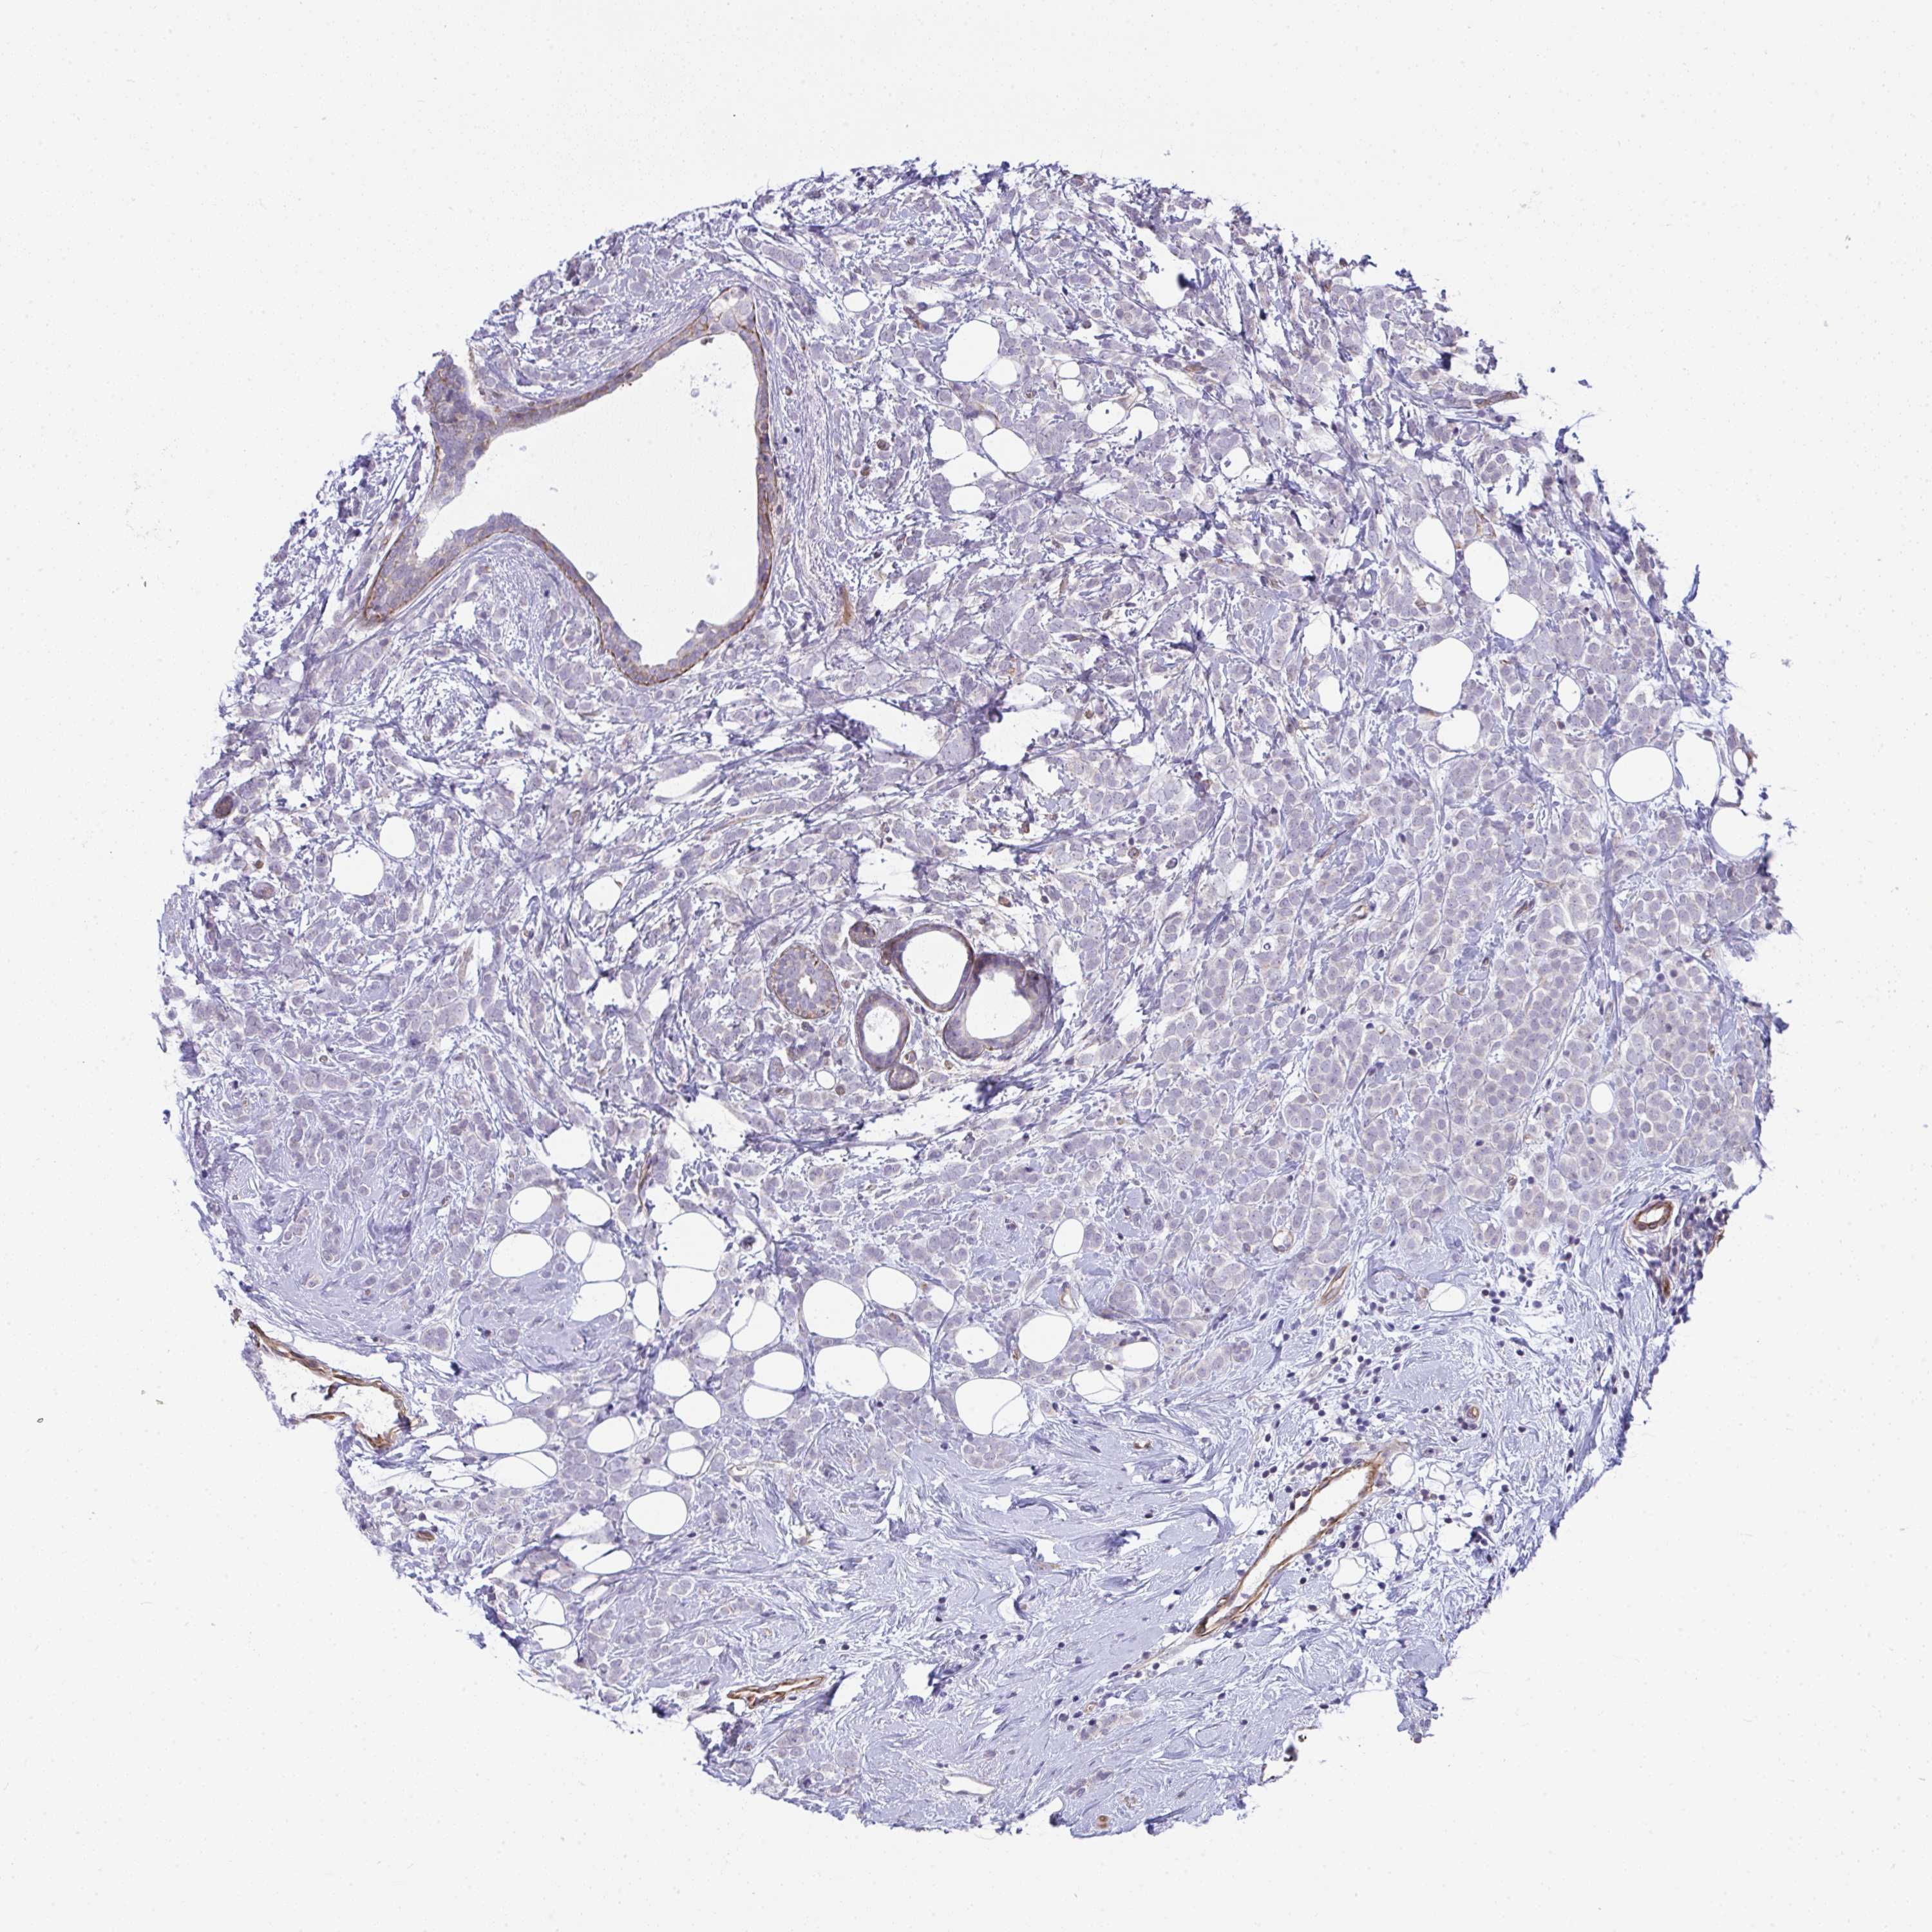

BRCA TCGA BRCA VALIDATION PROTEIN EXPRESSION